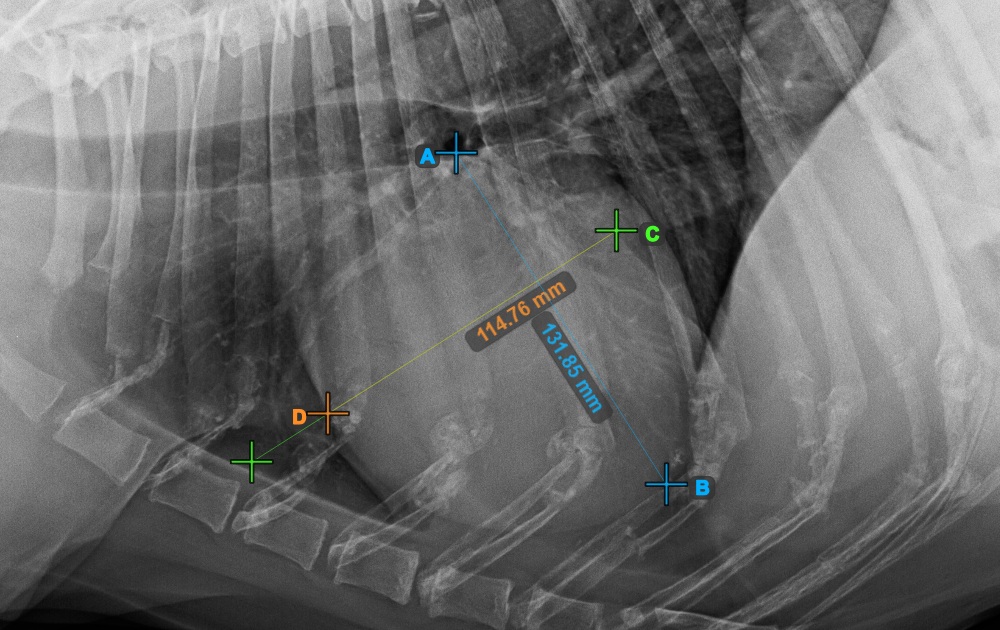

Fejezze be a szív rövid tengelyét a legszélesebb bal (caudal) pont megjelölésével.

Az alábbi kép a szív rövid tengelyének „legcaudalisabb” tipikus elhelyezkedését mutatja.